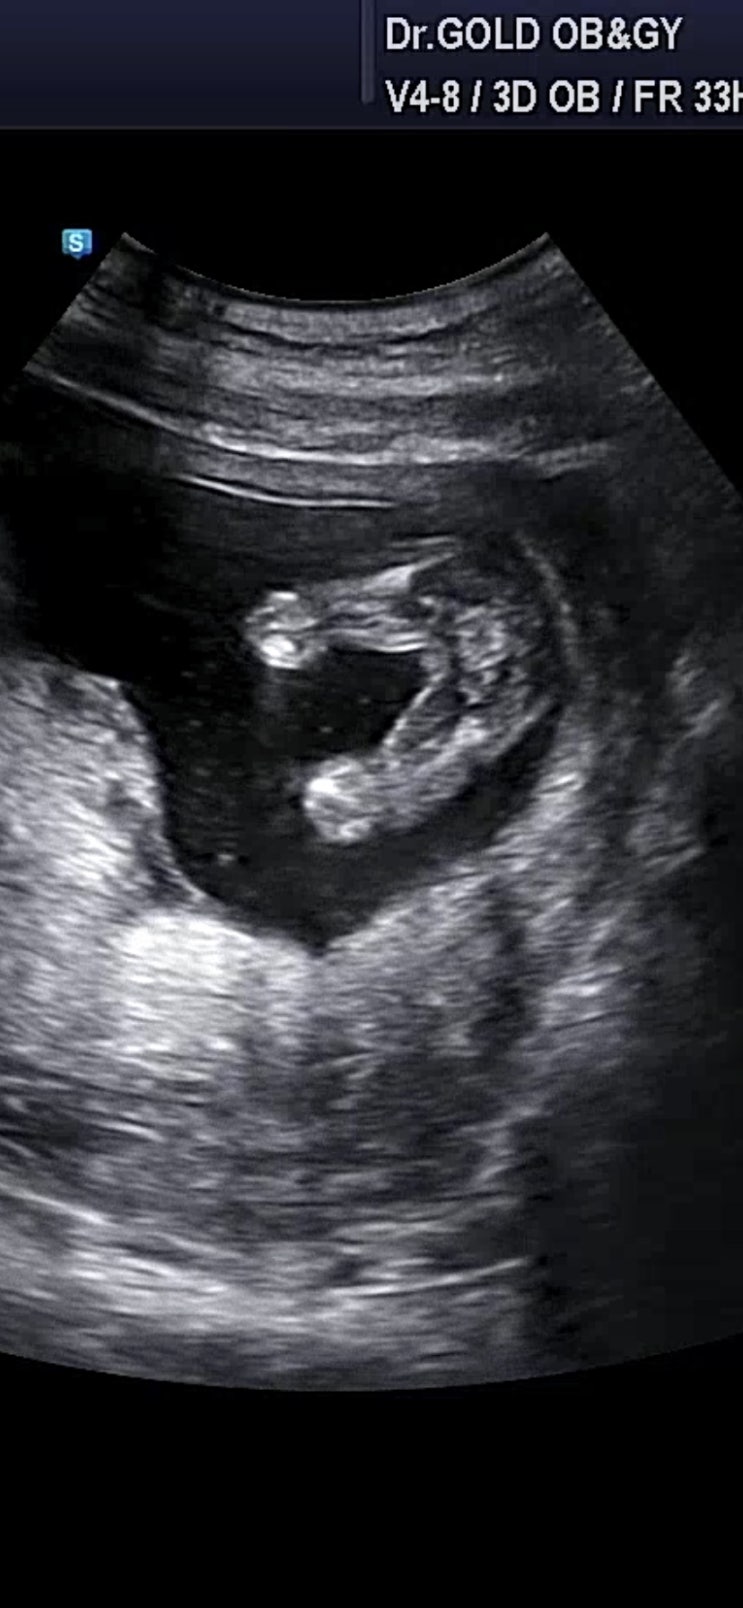

다솜이 첫만남

9/16일 첫만남 한번의 유산 다시 만난 소중한 아가 아프지말고 건강하게만 태어나다오 “애틋하게 사랑하는...

다솜이

10/4